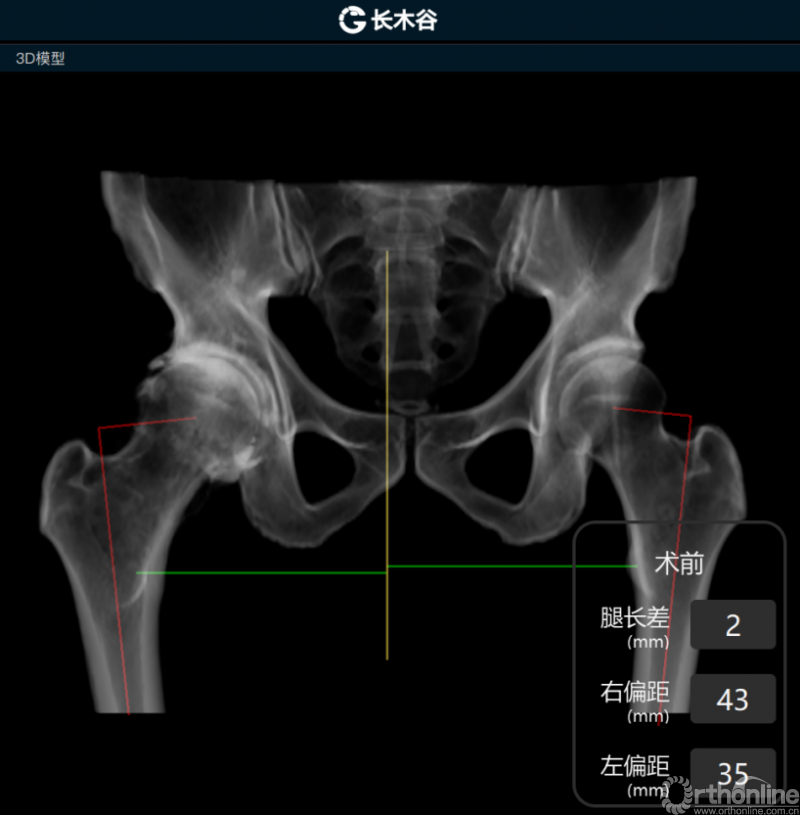

患者术前骨盆前后位X线片

AI HIP系统对患者术前偏距与腿长差进行智能测量与评估

而后,由人工智能判断患者双侧腿长差及股骨偏心距大小,如图可见,由于长期受到的髋关节撞击征影响,该患者术前腿长差为2mm,右侧股骨偏心距为43mm,明显大于左侧股骨偏心距35mm。